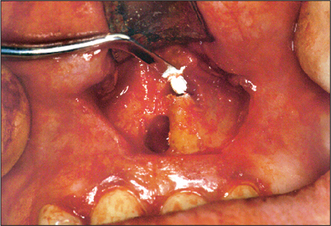

Bone removal

If there has been loss of buccal bone through pathological resorption, it is relatively simple to determine the site of bone removal. Otherwise, it may be possible to identify the apex of the tooth if a sharp probe is pushed through the buccal cortical plate to identify the pathological cavity around the tooth apex. A medium size (5 or 6) round bur is then used to create a window in the buccal bone and expose the apical tissues, including any granuloma (Fig. 6.8).

image

Fig. 6.8 Bone removal with a round bur, to expose the granuloma, after reflection of the flap.

If there has been no pathological resorption of buccal bone, the position of the tooth apex is determined using the average crown–root length for the tooth to be treated. Alternatively, the preoperative radiograph is used to work out the approximate crown–root length, taking into consideration the magnification factor of the X-ray apparatus used.

Page 75

It can be difficult to identify the apex during bone removal, especially if there is persistent oozing of blood from adjacent bone. Haemostatic material (e.g. oxidized regenerated cellulose) or a gauze swab soaked in local anaesthetic solution, packed gently into the bony cavity, may help to control bleeding if left in place for 30–60 seconds. The apex of the root may then be identified more easily. Once haemorrhage is under control, blood will ooze gently from the cut surface of the bone but not from the surface of the root, thus aiding its identification.